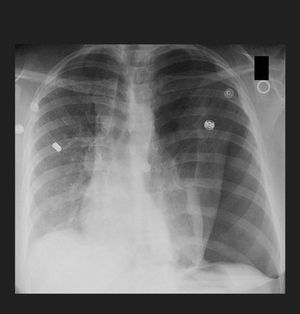

A 37-year-old male is brought to the emergency department following a motor vehicle accident. On arrival, respirations are shallow. Blood pressure is 80/60 mmHg, pulse is 122/min, and respiratory rate is 29/min. Physical examination demonstrates absent breath sounds on the patient's left side. Chest radiograph is shown. Which of the following is the most appropriate next step in management? A. Echocardiography B. Needle thoracostomy of the left second intercostal space C. Chest tube placement in the left fourth intercostal space D. Transfusion of packed red blood cells E. Endotracheal intubation

The correct answer is B. The patient's chest radiograph demonstrates a tension pneumothorax with collapsed lung. Needle thoracostomy in the left second intercostal space should be performed urgently. Tension pneumothorax is a medical emergency that occurs most frequently following trauma or lung infection. Physical exam findings include an absence of breath sounds on the side of the pneumothorax and hyperresonance to percussion in the ipsilateral lung. The injured lung acts like a one way valve such that air can enter the pleural space but cannot leave. Urgent needle thoracostomy is indicated to prevent cardiogenic shock and possible death. The Figure demonstrates a large left-sided tension pneumothorax. The mediastinum and trachea are shifted to the patient's right side. Answer C: Chest tube placement is indicated to prevent tension pneumothorax recurrence following needle thoracostomy.